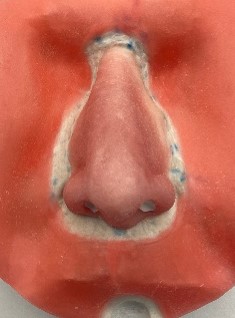

The Master of Science program in Clinical Anaplastology (CA) provides students with knowledge to succeed as clinicians providing facial, ocular (eye), and non-weight bearing somatic (body) prostheses, as well as designing 3D patient-matched models, surgical templates and other 3D printed clinical models.

- Examples of the work created